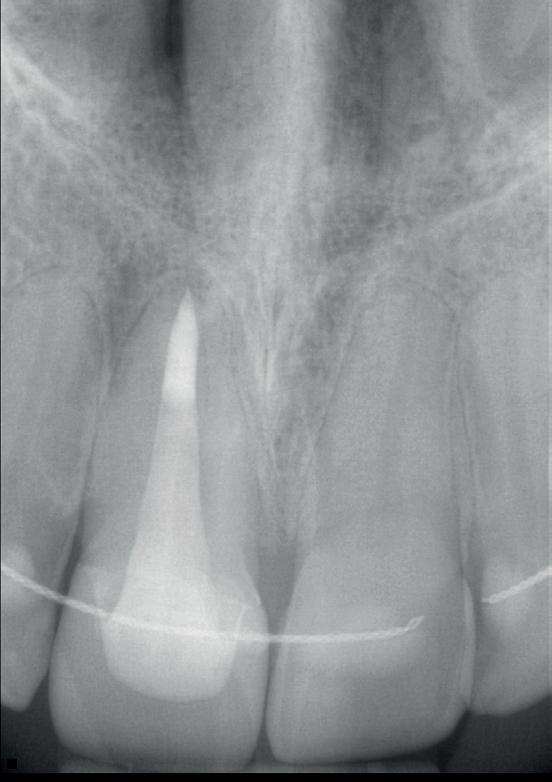

1: Klinische foto van bovenfront

2: Röntgenfoto van 11 met zilverstift sectie

3: Pocket palatinaal 11

4: Horizontale doorsnede CBCT met radiolucentie mesiopalatinaal van de 11

de patiënt zich zorgen maakt over deze toevalsbevinding, wil hij de 11 laten beoordelen door een endodontoloog.

Er wordt een CBCT gemaakt die een laesie aan de mesiopalatinale zijde van 11 laat zien (afbeelding 4).